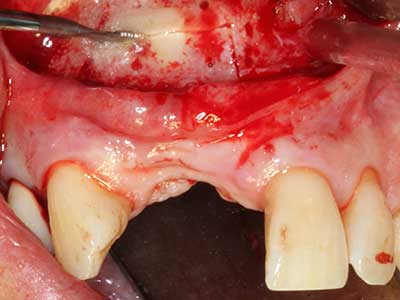

Knochengewebe ist nicht nur rein mineralisch, sondern auch in wesentlichen Anteilen aus Kollagenfasern aufgebaut. Dies gewährleistet neben einer guten Druckfestigkeit eine gewisse Flexibilität, welche für die Durchführung von Augmentationen genutzt werden kann. Bei der klassischen Expansionsplastik im Sinne eines Bone Splittings wird der atrophierte Kieferkamm in seiner Längsachse gespalten und nach Erreichen einer ausreichenden Osteotomietiefe vorsichtig aufgedehnt (Abb. 13-16), idealerweise ohne den Kiefer wesentlich zu deperiostieren (Brugnami, Caiazzo et al. 2014, Stricker, Fleiner et al. 2014). Bewährt haben sich Schrauben- und Plattensysteme mit zunehmender Expansionsdistanz, um die beiden Knochenlamellen unterhalb der Bruchschwelle voneinander zu distanzieren. In der Regel werden Restknochenbreiten von mindestens 3-4 mm gefordert (Chiapasco, Zaniboni et al. 2006), um eine ausreichende Flexibilität und knöcherne Bedeckung der einzubringenden Implantate zu gewährleisten. Ggf. kann eine ein- oder beidseitige vertikale Entlastungsosteotomie die Flexibilität verbessern. Als Alternative zur klassischen Technik wurde eine Kombination mit weiteren augmentativen Techniken vor allem auf der bukkalen Seite beschrieben.

Mittels Piezosägen erfolgt die Anlage des Splittings besonders schonend und ohne wesentliche Dimensionsverluste, so dass sich keine signifikanten Unterschiede von Implantaten im gesplitteten Kiefer im Vergleich zum nicht defizitären Alveolarkamm gezeigt haben (Chiapasco, Zaniboni et al. 2006, Danza, Guidi et al. 2009). Gerade beim lokal begrenzten und tiefen Splitting ist jedoch stets auf eine ausreichende Wasserkühlung zu achten, um thermische Belastungen in den apikalen Osteotomiebereichen zu vermeiden.